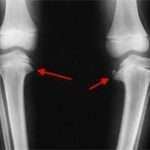

Хвороба Блаунта у дітей: ознаки і лікування

Зміст:Причини виникненняКлінічні проявиДіагностичні заходиПідходи до лікуванняХвороба Блаунта у дітей — це патологія, при якій спостерігається деформація верхніх відділів великогомілкової кістки.